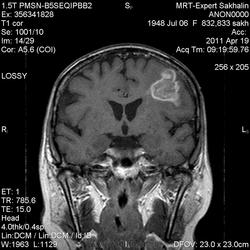

склоняюсь к кровизлиянию в левой теменной долей, начало перехода острой стадии в раннюю подострую( по периферии определяется повышение МРС по Т1 ВИ -метгемоглобин). Справа -старые кортикальные постишемческие глиозно-атрофические изменения. Контрастируется , вероятно за счет формирования участков ангионеогенза.

А мне кажентся больше за опухоль. Может быть сосудистая мальформация. Клинико-анамнестические данные есть?

Это демиелинизирующий процесс, острая стадия, причем с геморрагическим пропитыванием в центре пораженных участков. В принципе, соответствует тяжелому рассеяному склерозу, хотя может быть и геморрагическая форма ОДЭМ. Также могут быть мозговые проявления системного васкулита: надо знать анамнез.

На фоне ДЭП изменений МР-картина ОНМК по ишемическому типу в бассейне ЛСМА с участками геморрагического пропитывания. Аналогичный участок но в более поздней фазе в задних конвнкситальных отделах правой теменной доли.

О.С., я согласен, что контрастирование нехарактерно для ОНМК, ведь в подострую стадию инфаркта наблюдается, как правило, гиральный тип усиления. Плюс, на ОНМК непохоже то, что поражено почти только белое вещество, а кора интактна. И потом, при такой локализации инфаркта обязательно должна быть яркая клиника, и уж никак не только "головная боль".

Что касается снимочков мне кажется что зона патологического сигнала в левой гемисфере можно расценить как подострую стадию ОНМК с геморрагическим пропитыванием, справа как последствия ОНМК. При чем множественные очаги скорей всего как проявление ХМНК. И обязательно рекомендовать контрольное МРТ в динамике . Если это действительно ОНМК на фоне лечения отек уйдет и будет формированиться зона кистозно-глиозных изменений, а если отек будет нарастать значит надо думать о объемном процессе.

ОНМК по геморрагическому типу, почти классика.